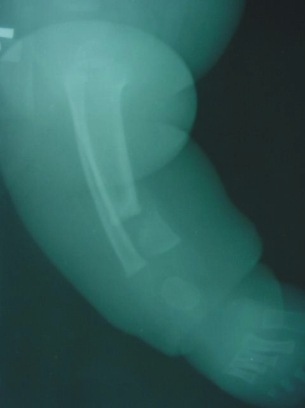

- Typ I – zagięcie przednio-boczne z prawidłowym kanałem szpikowym, prognoza dobra, może nigdy nie dojść do złamania

- Typ II - (sklerotyczny) – zagięcie przednio-boczne ze sklerotyzacją korówki i zwężeniem jamy szpikowej, wymaga ortezowania, prawdopodobne złamanie, przewidywane leczenie operacyjne

- Typ III - (cystyczny v. torbielowaty) – Zagięcie przednio-boczne ze zmianami torbielowatymi w okolicy zagięcia, wymaga wczesnej interwencji operacyjnej ze względu na częste złamania z następczym stawem rzekomym

- Typ IV - (dysplastyczny) – najgorsze rokowanie, zagięcie przednio-boczne ze złamaniem i stawem rzekomym, z wrzecionowatym zwężeniem kości w obrębie stawu rzekomego, z całkowitym lub częściowym zamknięciem kanału szpikowego.

- śródszpikową stabilizację (gwoździe blokowane, pręty endera, TEN) Jeśli staw rzekomy jest blisko nasady do rozważenia jest założenie wszczepu śródszpikowego przezpiętowo. Zyska się w ten sposób dodatkową stabilność fragmentu dystalnego jednak kosztem późniejszych zaburzeń w obrębie stawu skokowego (Obu)